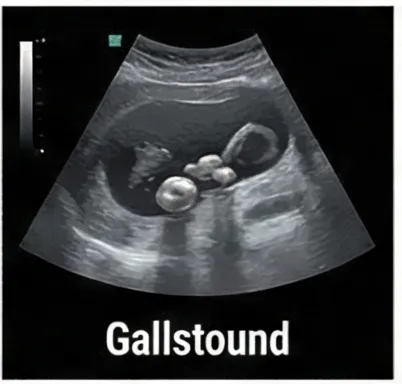

• 담석증 - 담도 질환 위험 증가